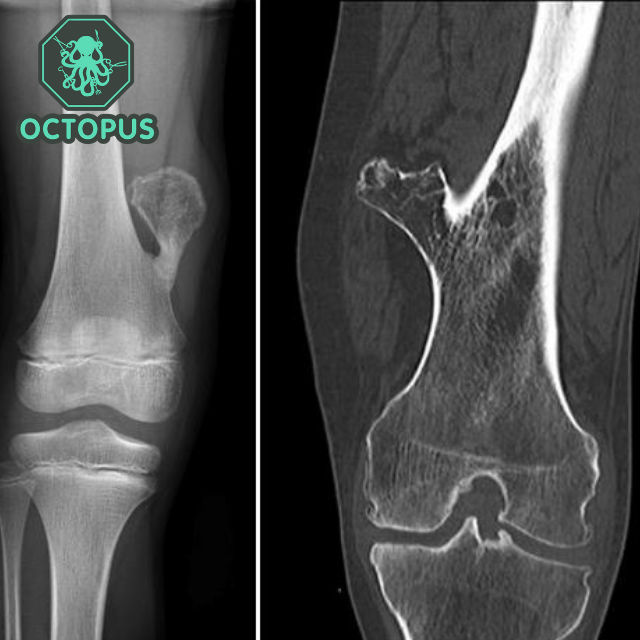

Экзостоз Кости Фото

Экзостоз Кости Фото 114 фото